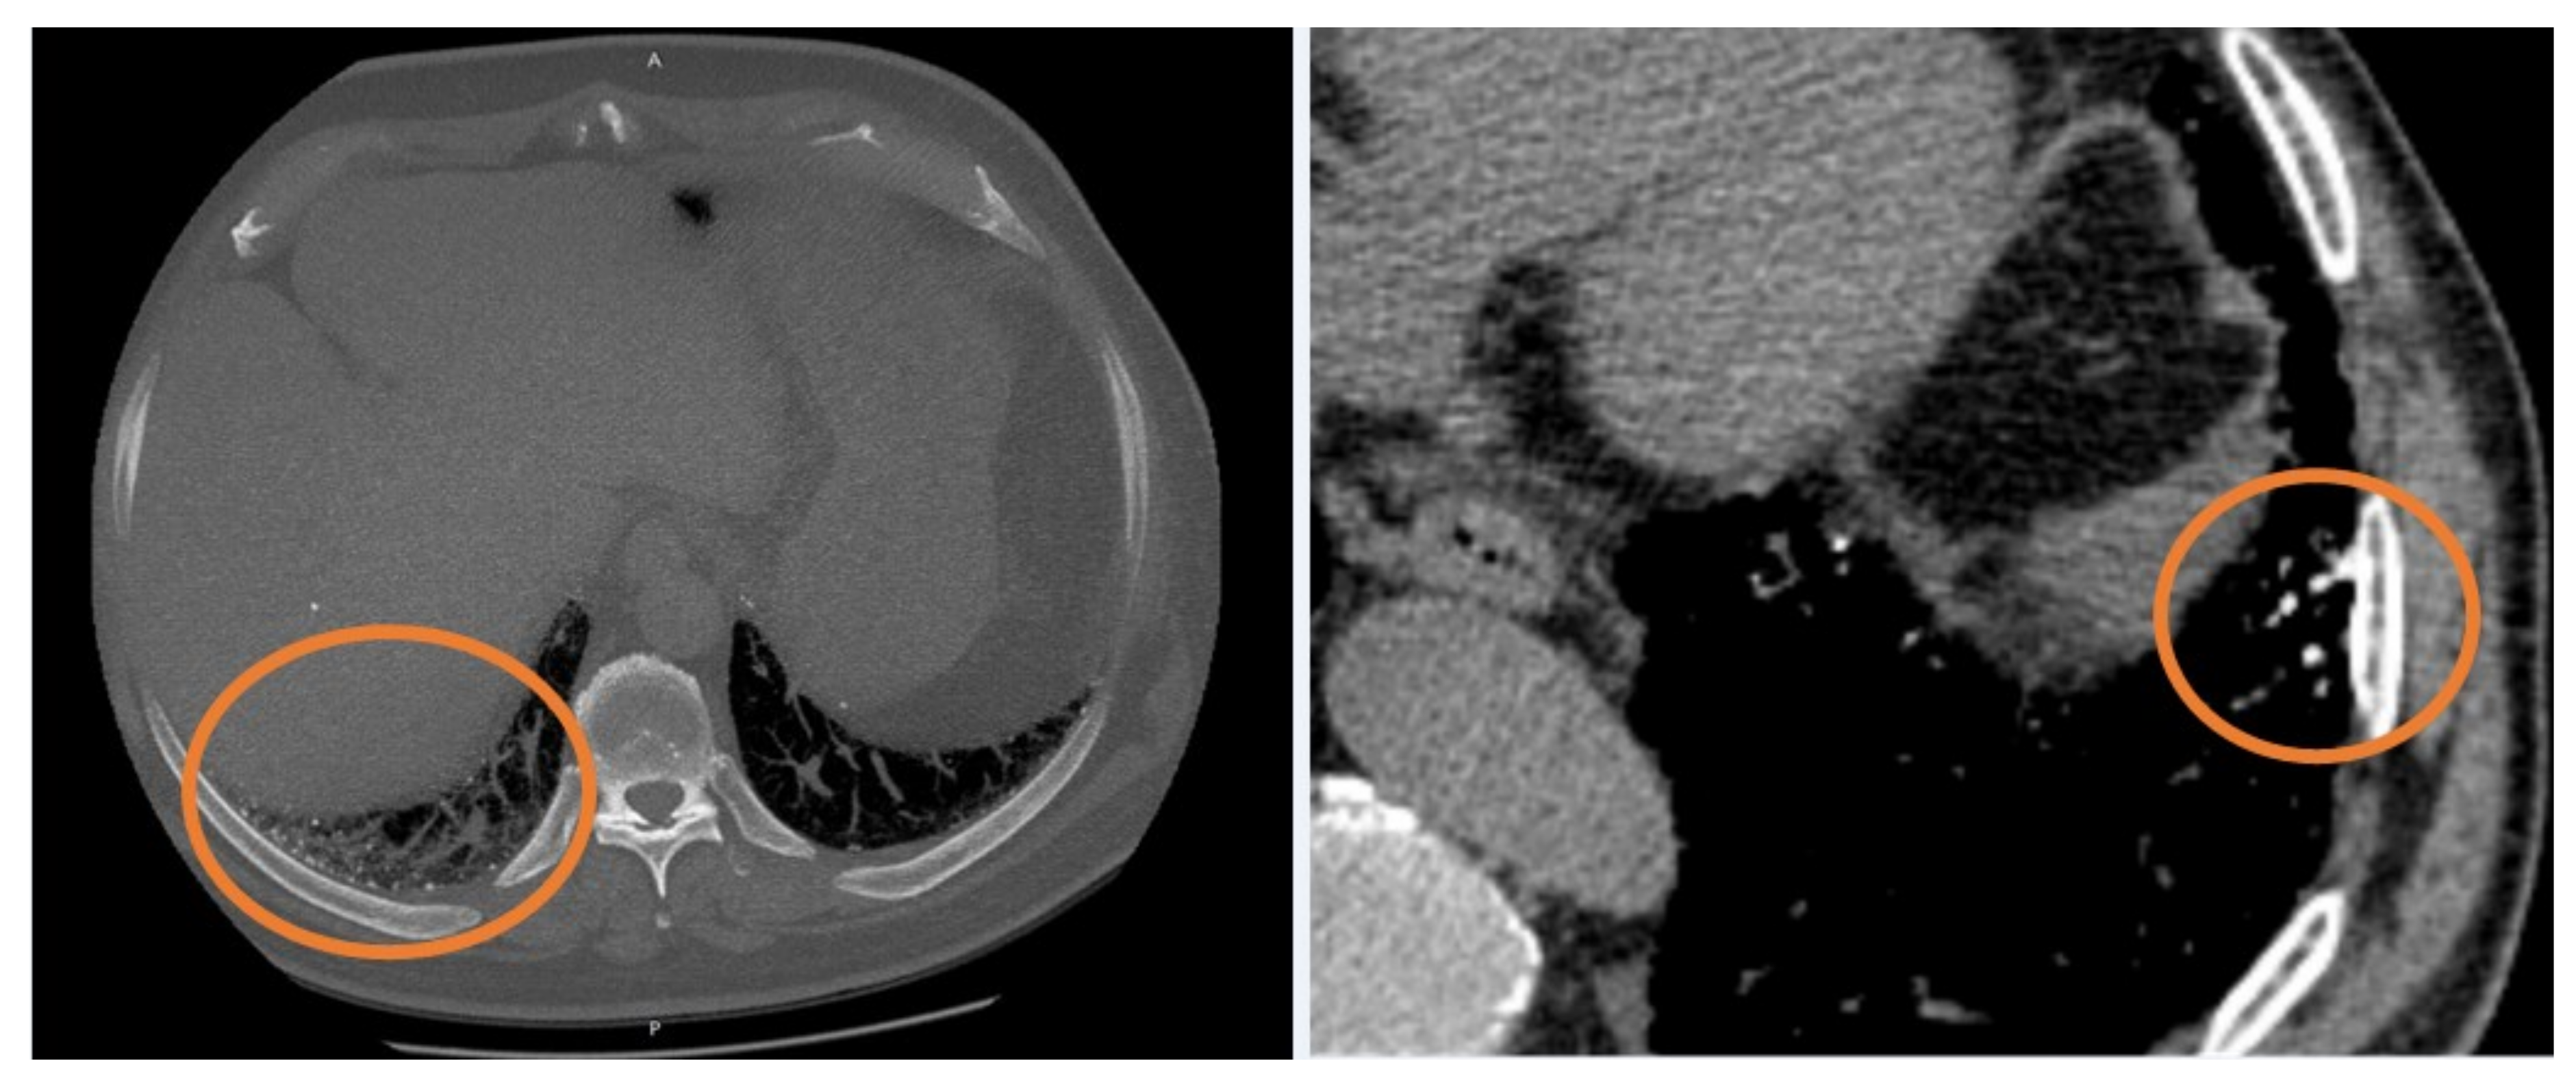

Figure 1. Two examples of dendriform ossification (orange circles), localized in subpleural regions.